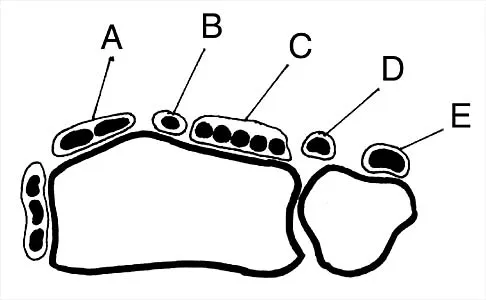

Figure 30 shows an axial cross section of extensor tendon anatomy in zone 7 of the wrist. What letter best depicts the location of the posterior interosseous nerve?

Explanation